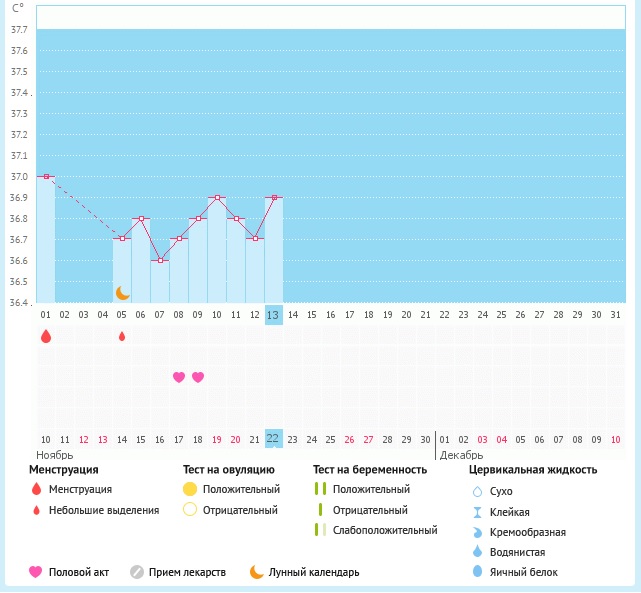

Была сегодня на УЗИ, 12 ДЦ, думала перед О сходить, а получилось что она уже была. Это конечно хорошая новость, что О вообще есть, а вот остальное не порадовало.

В общем ниже УЗИ, гормоны на 5 ДЦ и график БТ. Что скажете?

График в этом цикле не красивый(

Вопрос когда была О можно понять? Хотела прогик сдать, а теперь даже не знаю на какой ДЦ сдавать.

Похоже на 7 дц, но почему вчера так упала бт... Можно было б еще предполржить, что вчера, но по гормонам видно, что уже вторая фаза. А узи и гормоны когда сдавали? И как на 7дц як могла перезреть?) Падение вчера вдруг ИЗ?

Эм... Вообще непонятно... Либо О в месяки пришла, либо все ж на 7 дц, а на 5й у вас всплеск ЛГ как раз перед овулей) ну это все, что в голову приходит. По идее теперь и мес раньше должны прийти. День на 19-21.

Сердечко должно быть в ночь с 7 на 8 дц, просто поставила на 8. Но даже если и попали в О на 7дц, я очень сомневаюсь в положительном результате с таким эдиком (

Дополню. Цикл 26-27 дней. Ни болей, ни непонятных выделений. По тестам на О, ощущениям и БТ овуляция обычно на 13-14 ДЦ. В этом цикле по ощущениям О была вообще на 7 ДЦ, но это вряд ли, видимо подвели ощущения.